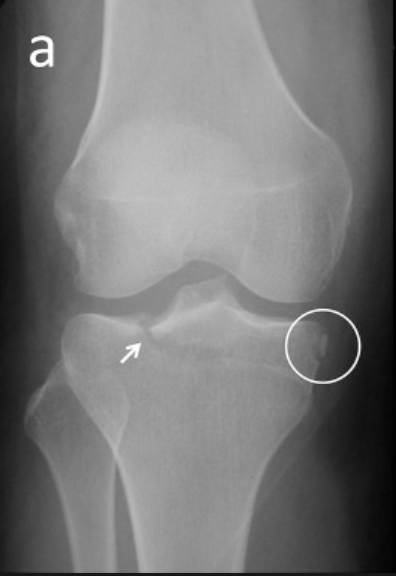

Defina a lesão de Segond Reverso

A

Avulsão da borda anteromedial do platô da tíbia, indica lesão do LCP